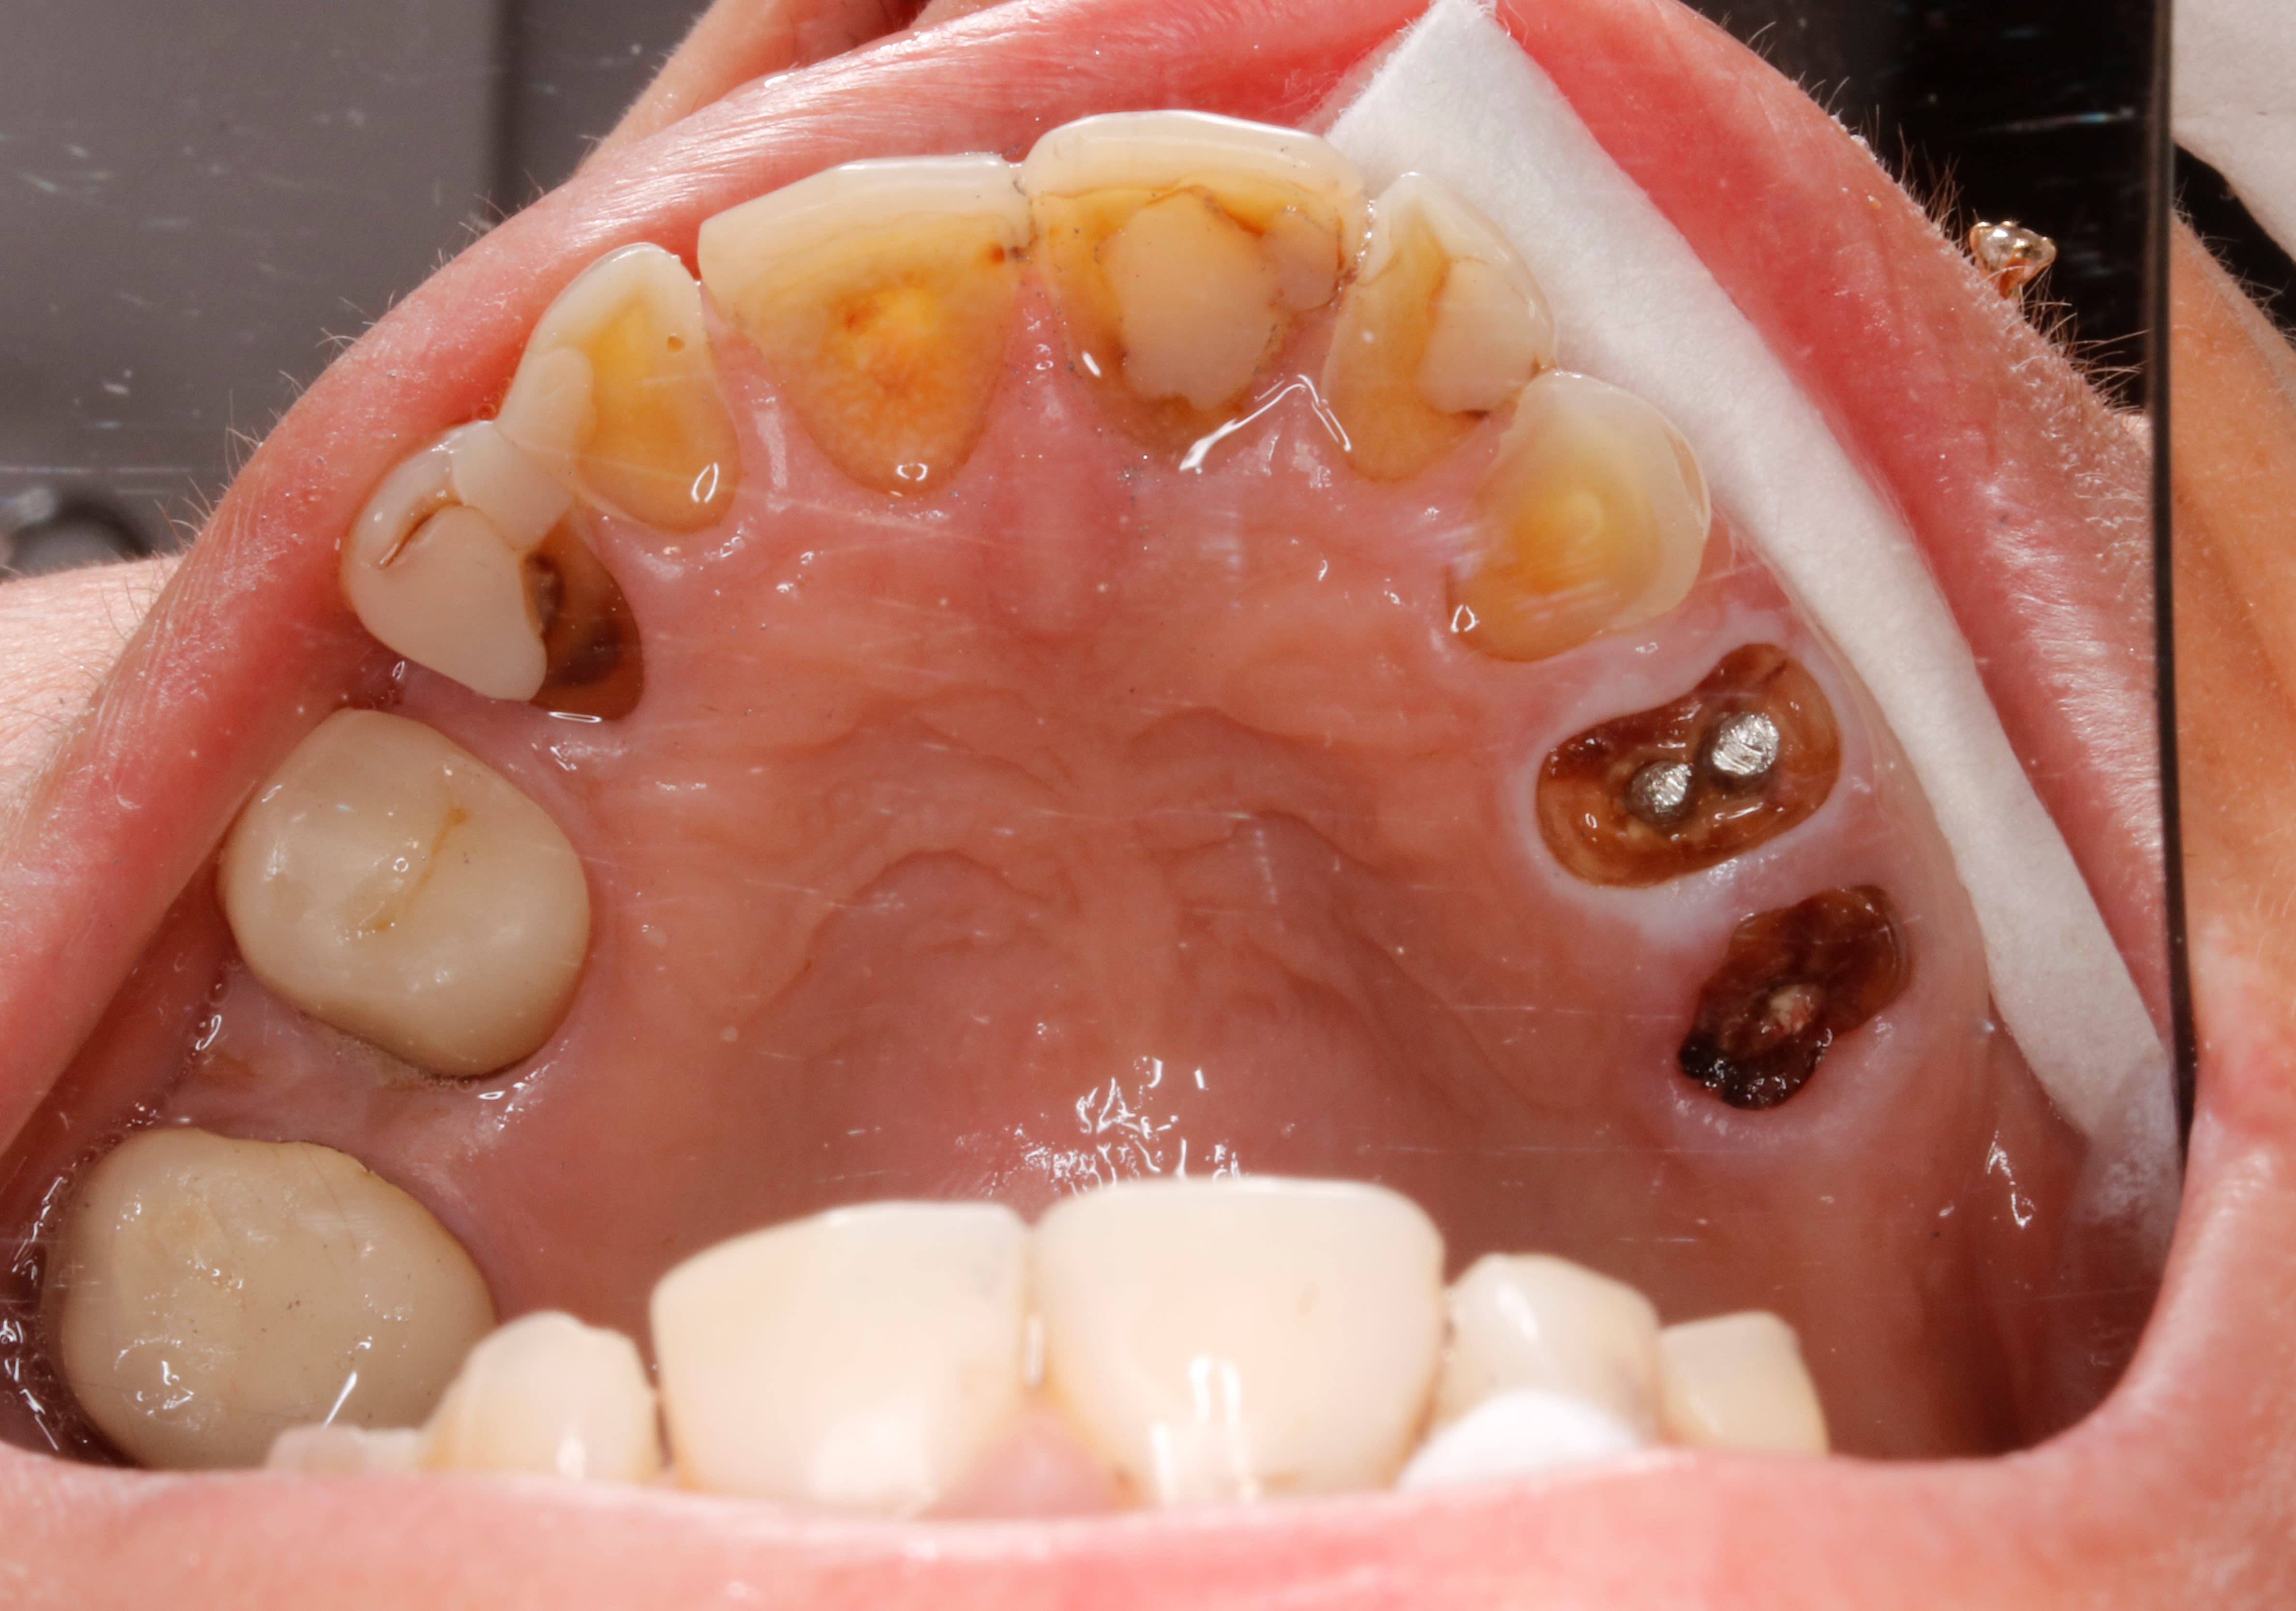

tu vois la 25 ? , ( photo au miroir ) oui celle toute tordue .

elle est tordue pcqu elle a perdu la 24 , et plein d autre d ailleurs , depuis que je ne l ai plus revue .

bon , en plus on ne peut pas dire qu elle ait une occlusion favorable hein !